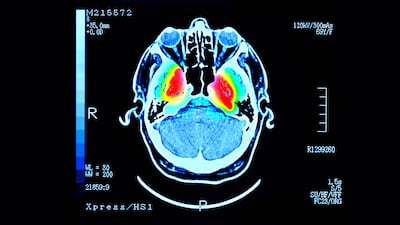

Aggregations of this in the brain, called Lewy bodies, are associated with Parkinson’s and related neurodegenerative disorders.

Dr Magzoub said that mice treated with SK-129 had “far fewer” protein aggregates in their brain than mice that had not been treated.

In Parkinson’s patients, changes in the brain cause deficiencies of the neurotransmitter dopamine in certain brain structures, resulting in physical symptoms, such as tremors and other problems, including sleep disorders and cognitive changes.